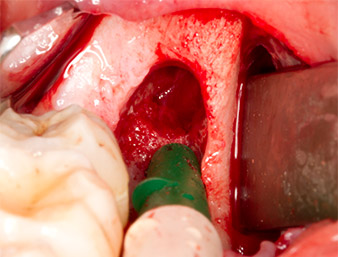

Per ottenere materiale autogeno per il successivo trattamento della ferita, sono stati estratti frammenti di osso sano nella zona del residuo di radice con uno strumento piezochirurgico (Piezomed B5) (Fig. 5).